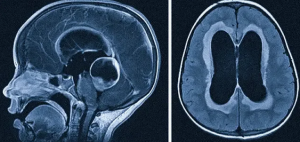

В автоматическом режиме была проведена МР-морфометрия с определением морфометрических показателей (объема в мм3, площади в мм2 и толщины в мм) для каждой структуры височных долей, представленной на рис. 1.

Статистический анализ проводился с использованием программного обеспечения Jamovi 2.3.28 и Microsoft Excel 2007 [28, 29]. Для анализа полученных результатов и выявления статистически значимых различий между группами были применены соответствующие методы статистического анализа. Количественные данные были описаны с использованием среднего значения и стандартного отклонения. При сравнении средних значений двух возрастных групп для количественных переменных использовался непараметрический U-критерий Манна-Уитни, что позволило учесть возможные выбросы и асимметрию в данных. Графическое изображение полученных результатов сегментации структур головного мозга с помощью программного пакета FreeSurfer показано на рис. 2 и рис. 4. Был проведен анализ линейной регрессии и определено процентное изменение средних значений для оценки трендов в изменении морфометрических показателей (объема в мм3, площади в мм2 и толщины в мм) структур височных долей. Для вычисления процентного изменения средних значений использовали формулу:

Общие изменения структур височных долей. Процентное изменение средних значений объема (мм3), площади поверхности (мм2) и толщины структур (мм) височных долей при сравнении исследуемых возрастных групп представлено в табл. 2, на рис. 2 и 3.